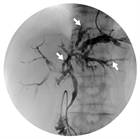

1. PSCとIgG4関連硬化性胆管炎との鑑別診断のためにERCPなどの直接胆管造影を行うことが推奨される(推奨度2、OJ)

1. PSCの診断のためにMRCPを行うことは強く推奨される(推奨度1、RSJG)